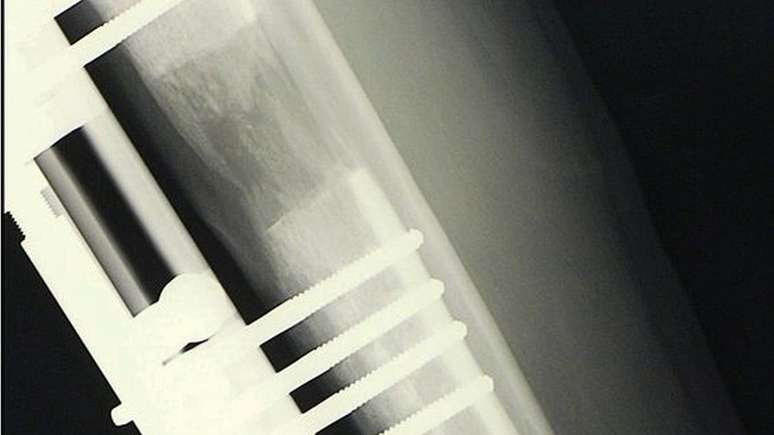

A cirurgia consiste em quebrar o osso e separá-lo sutilmente com o auxílio de uma barra

Conforme explicam vários cirurgiões consultados pela BBC, o tratamento padrão é o seguinte: primeiro, é feito um furo nos ossos da perna, que depois são divididos em dois.

Em seguida, uma haste de metal é colocada cirurgicamente no osso e mantida no lugar por uma série de parafusos.

A haste é lentamente alongada em até 1 milímetro por dia, estendendo-se até que o paciente atinja a altura desejada e seus ossos sejam deixados para cicatrizar novamente.